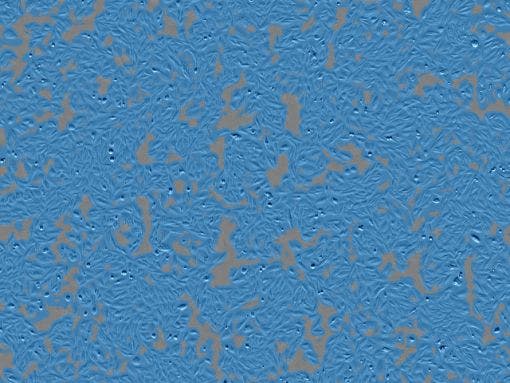

Células humanas adenocarcinomatosas del epitelio basal alveolar (A549)

Condiciones del recipiente: Placa de 12 pocillos. Tiempo de intervalo: 1 hr. Período de medición: 4 días. *Adquisición con modo personalizado.

Recuento de células : 3.42 × 10³

Confluencia : 70.60%

Resultados analíticos